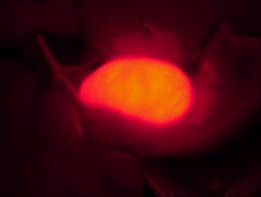

[客戶實(shí)驗(yàn)方法] 以小白鼠作為實(shí)驗(yàn)動(dòng)物模型,通過體視熒光顯微鏡觀察實(shí)驗(yàn)組和對(duì)照組,在同一參數(shù)設(shè)置下,用明美成像系統(tǒng)分析軟件將明場(chǎng)、熒光分別拍攝的效果圖合成,檢測(cè)藥物作用部位。

對(duì)照組:

對(duì)照膽明場(chǎng)

對(duì)照組熒光(無(wú)成像)